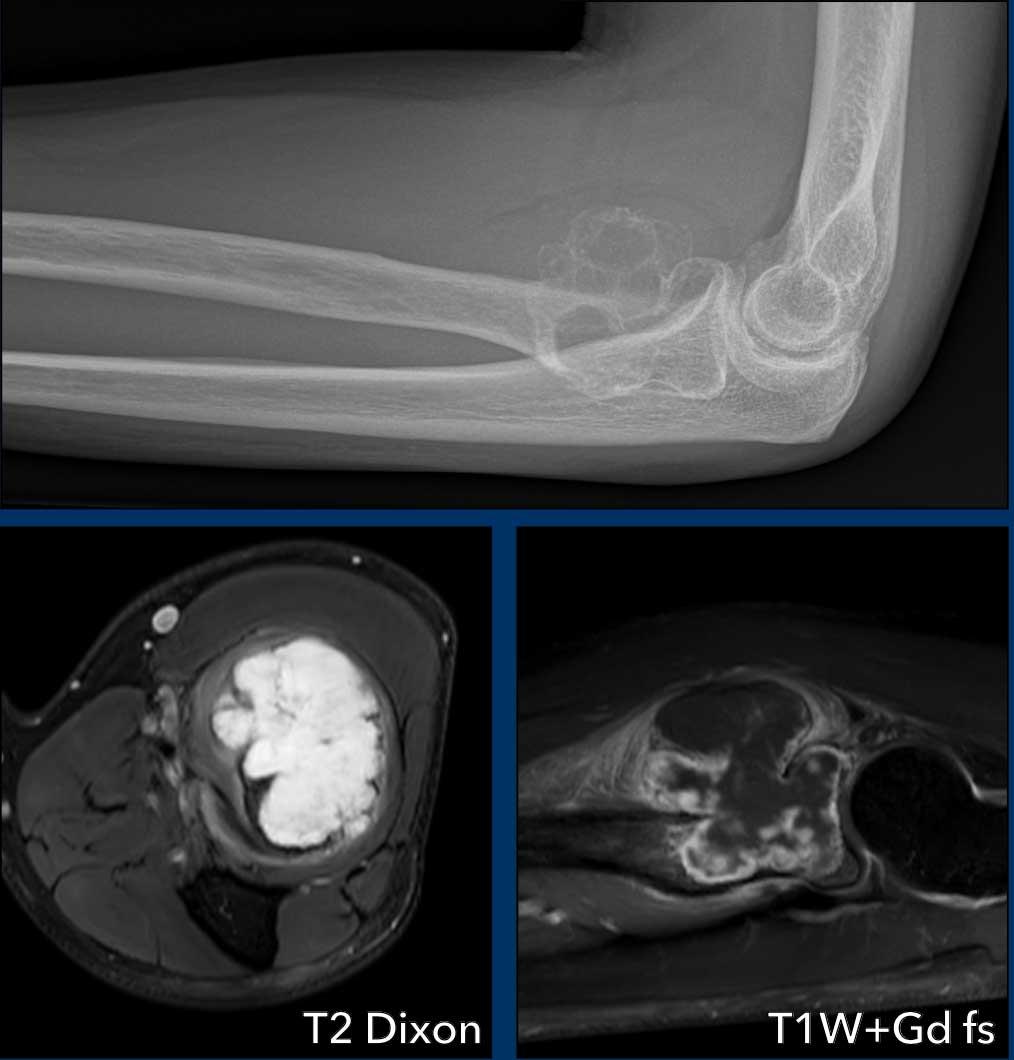

Phim X-quang cho thấy tổn thương tiêu xương dạng đa ổ, có tính chất giãn rộng tại vùng hành xương đầu gần xương quay.

Có thể thấy một số chấm vôi hóa nhỏ bên trong tổn thương.

Khối u tăng tín hiệu trên chuỗi xung T2 DIXON và có các vùng phá hủy vỏ xương.

Sau tiêm thuốc cản quang, xuất hiện hình ảnh ngấm thuốc điển hình dạng vách-nốt và các vùng chất nhầy không ngấm thuốc, cũng hiện diện trong thành phần phần mềm.

Xung quanh khối u có hình ảnh phù nề phần mềm.

Những đặc điểm này giúp chúng ta đưa ra chẩn đoán u sụn ác tính độ cao (chondrosarcoma độ cao).

Kết quả giải phẫu bệnh sau cắt rộng cho thấy sarcoma sụn độ II.